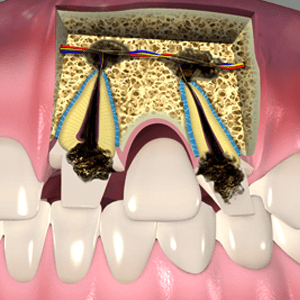

Endodontic Surgery

Most of the times root canal treatments are successful and the tooth is free from dental problems for the rest of the life. In some cases when the infection persists after the procedure endodontic surgery may be necessary. An endodontist suggests a surgical treatment when there are signs of infection around the root which is difficult to reach through commonly used dental instruments. Apicoectomy is one of the commonly performed surgeries by the endodontist. The infected tissues from the root end are removed and the area is filled with inert filling material. Other complex surgeries performed by the endodontist are processes which involve repair and removal of roots.